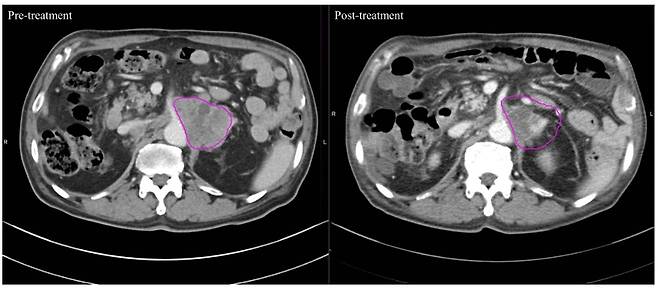

24일 국제바이러스연구연합(IVRA) 조직위원회에 따르면 장홍석 서울성모병원 방사선종양학과 교수 연구팀은 2019년 1월부터 2022년 3월 말까지 고온 온열치료 환자 20명과 방사선 단독 치료 환자 20명 등 전이성 복부 림프절 치료 환자 총 40명을 대상으로 컴퓨터 단층촬영(CT) 이미지를 모았다. 그리고서 치료 전후 종양 괴사의 변화를 관찰하는 지표(하운스필드 단위·Hounsfield Unit·HU)값의 변화를 비교해 치료 효과를 평가했다.

그랬더니 고온 온열치료 그룹은 치료 후 HU 값이 평균 9.05%(-8.47HU) 낮아진 58.95로 나타났다. 반면 기존의 방사선 치료 그룹은 0.57%만 줄어든(-0.41HU) 71.42였다. 이번 연구 결과는 최근 국제학술지 '플러스 원(PLOS ONE)'에 발표됐다.

이번 연구에서 장홍석 교수는 전이성 복부 림프절 치료 환자를 대상으로 의료용 고주파 온열기 '리미션'을 활용한 '고온 온열치료', 저온에서 중간 용량의 '방사선 치료' 중 발생하는 종양의 변화를 비교 평가했는데, 온열치료가 암 사멸에 더 효과적인 것으로 나타났다. 리미션 개발사인 아디포랩스에 따르면 리미션은 고주파가 1초에 46만 번 파장을 일으키면서 심부열(몸속 조직의 온도)을 발생시킨다. 열이 발생하면 정상조직은 주위 혈관이 늘어나면서 혈액을 순환시키며 열을 분산한다. 하지만 암세포는 혈관 확장 능력이 떨어져, 열을 분산하지 못하고 결국 점차 괴사한다.

장홍석 교수는 "다른 치료가 효과가 없는 말기 암 환자들을 대상으로 온열치료 데이터를 6년 정도 모아 연구했다"면서 "온열치료를 시행하면 암 덩어리 괴사가 훨씬 더 빨리 일어나 방사선 치료보다 효과가 더 좋을 수 있다는 것이 논문의 핵심"이라고 말했다.